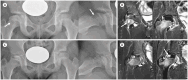

Developmental dysplasia of the hip is a condition characterized by hip joint instability due to acetabular dysplasia in infancy, necessitating precise ultrasound examination. Legg-Calvé-Perthes disease is caused by a temporary disruption in blood flow to the femoral head during childhood, progressing through avascular, fragmentation, re-ossification, and residual stages. Slipped capital femoral epiphysis is a condition where the femoral head shifts medially along the epiphyseal line during adolescence due to stress, such as weight-bearing. Differentiating between transient hip synovitis and septic arthritis may require joint fluid aspiration. Osteomyelitis can be associated with soft tissue edema and osteolysis. When multiple lesions are present, it is essential to distinguish between Langerhans cell histiocytosis and metastatic neuroblastoma. This review will introduce imaging techniques and typical findings for these conditions.